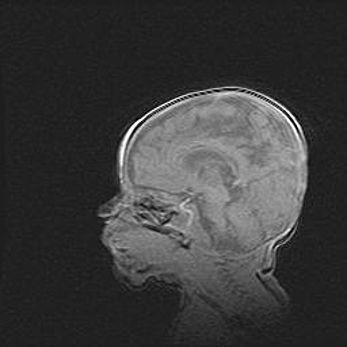

Мальформация Денди-Уокера. Киста задней черепной ямки.

Агенезия мозолистого тела.

Возраст: 2,5 месяца

Вес: 2420 г

Пол: женский

Окружность головы: 37 см

Срок гестации: 32 недели

Мальформация Денди—Уокера — редкий вид патологии ЦНС, представляющий собой врожденный порок развития каудального отдела ствола и червя мозжечка, ведущий к неполному раскрытию срединной (Мажанди) и латеральных (Лушка) апертур IV желудочка мозга. Для этогно синдрома характерна триада симптомов: гипотрофия червя мозжечка и/или полушарий мозжечка, кисты задней черепной ямки, гидроцефалия различной степени. В 70% случаев порок сочетается и с другими аномалиями головного мозга, в частности с агенезией мозолистого тела.